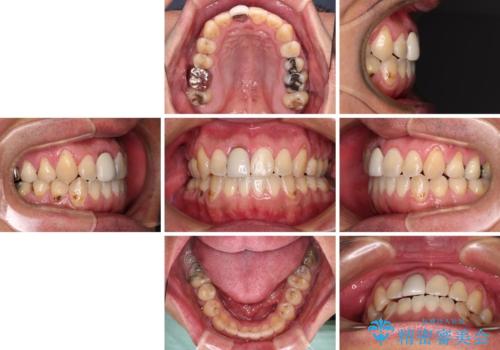

前歯のデコボコとクロスバイトをインビザライン矯正で改善

- 前歯のデコボコと上下のクロスバイトを気にして来院された患者様です。

インビザラインを用い、IPR(歯と歯の間を削る)と歯列全体を拡大させることで、歯並びを整えていくこととしました。

上の前歯が下の前歯を乗り越える際、奥歯がほとんど咬めない時期があり、乗り越えた後も、インビザライン特有の奥歯の咬みにくさが続きました。

咬み合わせ改善のために治療期間を要しましたが、最終的に奥歯はしっかりと咬めるようになりました